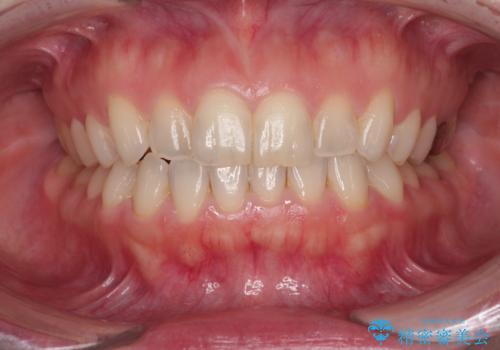

- 奥歯の銀歯をセラミックにしたいとのことで来院された患者様です。

当初は奥歯のみの治療をご希望でしたが、話を進めていくうちに、軽度ではあるものの、幼少期の薬の影響で歯が変色していることがコンプレックスであるということが分かりました。

長年歯の色が塞ぎ込んでいた部分があるとのことで、これを機会に全ての歯を真っ白にするために、オールセラミッククラウンにて補綴治療を行うこととしました。

より白さが目立つように、自然な仕上がりではなく、作り物の雰囲気があるフルジルコニアクラウンにて補綴治療を行いました。